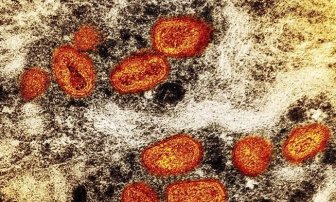

Monkeypox In Canada

Canada hasn’t needed to declare monkeypox an emergency, top doctor says. Here’s whyCanada already has mechanisms, including vaccines and treatments, in place to tackle the monkeypox outbreak amid signs of cases slowing down, Dr. Theresa Tam said.CanadaAug 12, 2022

Monkeypox risk in Hamilton ‘very low’ as cases surpass 1K in CanadaHamilton Public Health is characterizing the risk of getting monkeypox as minimal among the general public with only a handful of reported cases.HealthAug 11, 2022

Alberta expands eligibility of monkeypox vaccineThe Alberta government is expanding the eligibility criteria of the monkeypox vaccine to those at high risk for exposure to the virus.HealthJul 28, 2022

Monkeypox: Canada’s top doctor urges those at risk to get vaccinated as cases climbMonkeypox, which causes flu-like symptoms and skin lesions, is transmitted to humans from animals caused by an orthopoxvirus, which is related to smallpox, according to PHAC.CanadaJul 27, 2022